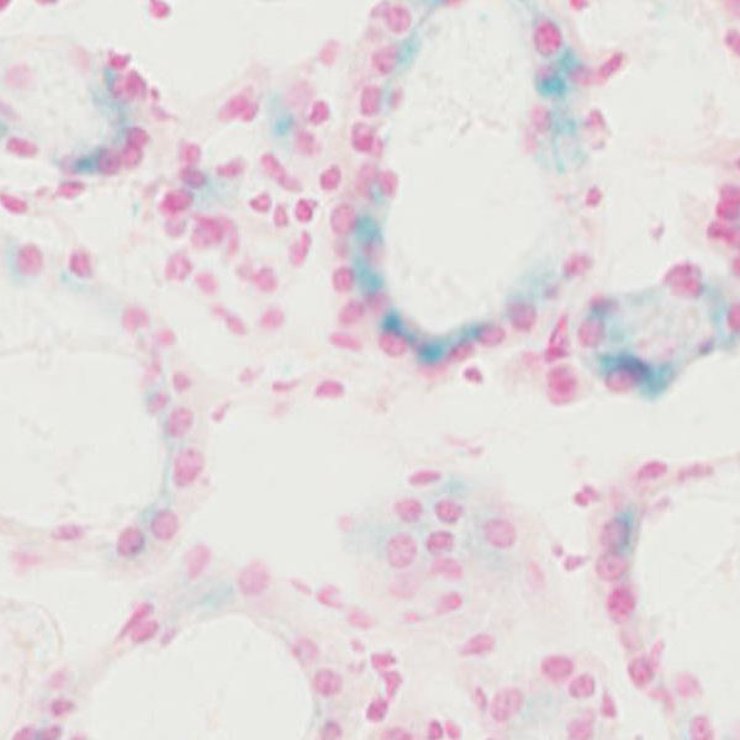

TS28: testis Present JAX_1305961

TS28: thyroid gland Present JAX_1305960

TS28: submandibular gland Present JAX_1305959